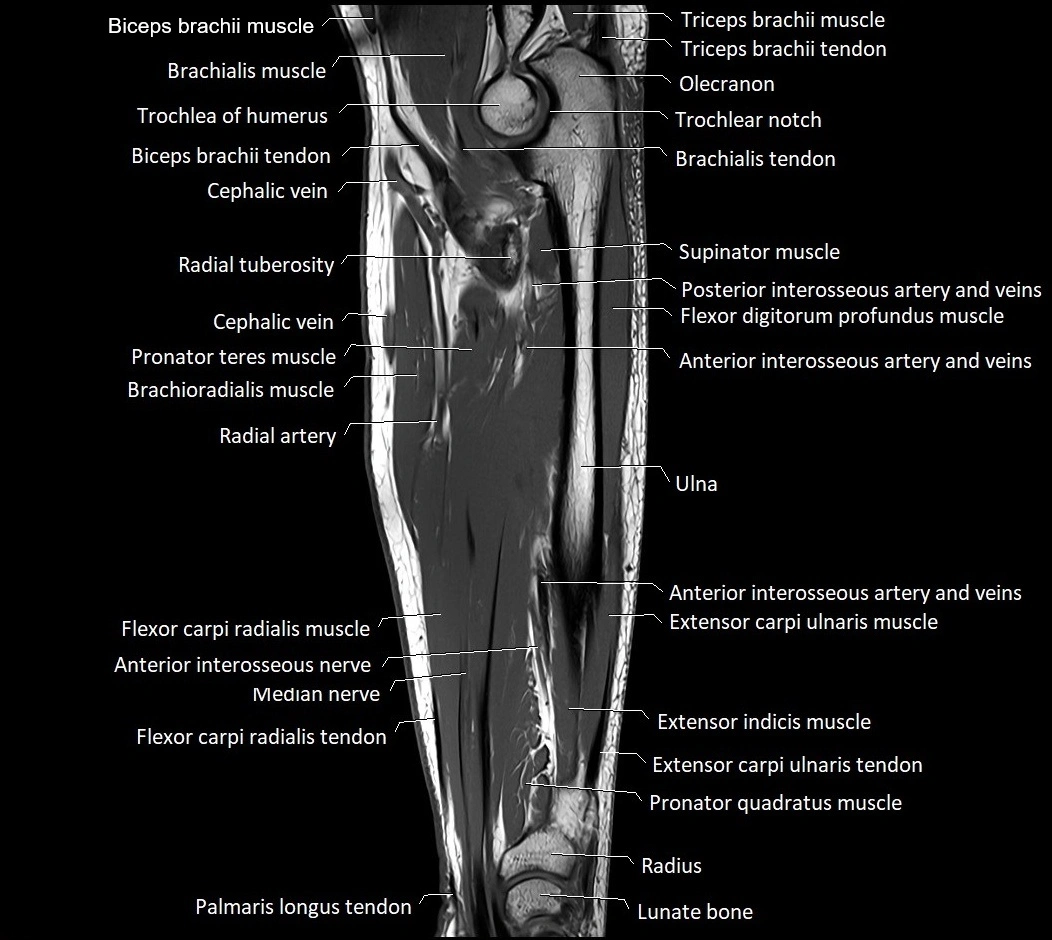

MRI images

image